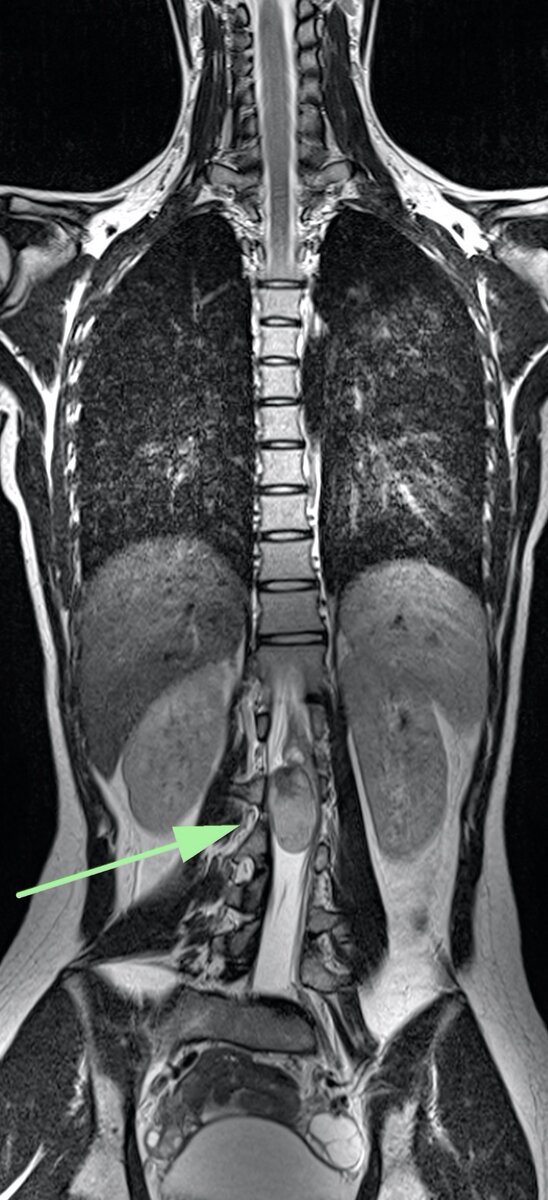

На МРТ обнаружена крупная опухоль конуса спинного мозга на уровне L1-L2 поясничных позвонков, тотально стенозирующая позвоночный канал. Структура опухоли неоднородная, с жировым компонентом. Спинной мозг и нервные корешки, идущие к ногам сдавлены. Это объясняет все её неврологические проблемы. Размер опухоли ≈ 6*3*3 см. Тем не менее, опухоль на МРТ выглядела доброкачественной, предположил дермоидную кисту.

Чтобы не терять время, сразу же дообследовали в в/в контрастным усилением.

Кракая справка: дермоидная киста (Dermoid cyst) - доброкачественная опухоль, в 20% процентов случаев возникает в нижних отделах спинного мозга. Пациенты обычно моложе 20 лет. Клинические проявления различные, в зависимости от размера опухоли; если её размер маленький то проявлений может не быть.

Золотой стандарт диагностики у таких пациентов - МРТ.

Опухоль, как правило, имеет характерную структуру с включениями жира, что отлично видно на МРТ.